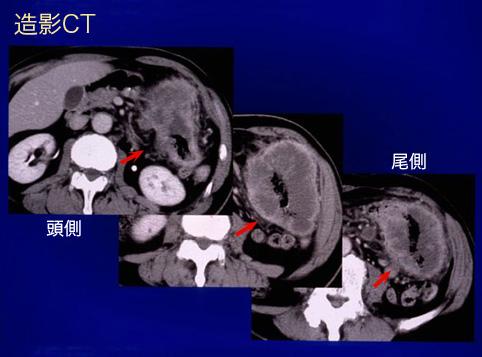

疾患(病理主体)の分類悪性上皮性腫瘍/腺癌

部位(臓器別)大腸/横行

検査方法CT

腫瘍の肉眼分類3型(潰瘍浸潤型)/

病変の最大径(ミリ)40以上

腫瘍の深達度s(a)